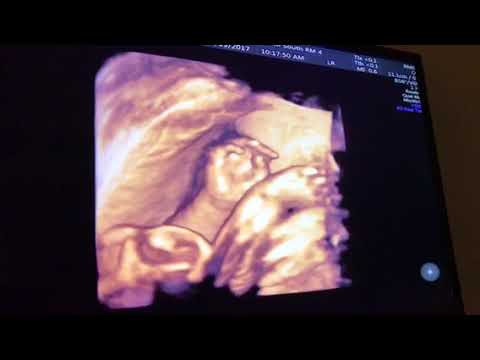

At this doctor's office, they offered 3D images of baby in the belly. While some photos looked a little creepy (you know - cut off limbs, hollow eye sockets and an overall lumpiness), it was interesting to see him move around in there. It's like we got a glimpse at his personality before we actually met him! Stephen and I ask the doctor how "accurate" these pictures were and if he'd look similar to this when he came out. I feel like we got our answer pretty quick. Take a look for yourself!

3D in the belly:

It's pretty amazing how similar these two videos are. You can see in the real life version that his mannerisms and movements are almost exactly like those seen in the 3D version. Crazy!